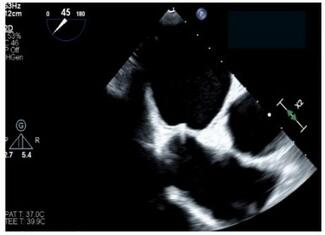

The authors report the case of an 88-year-old woman with paroxysmal atrial fibrillation, sick sinus syndrome status post-permanent dual chamber pacemaker, elevated thromboembolic risk, severe aortic stenosis, and a history of bleeding that...